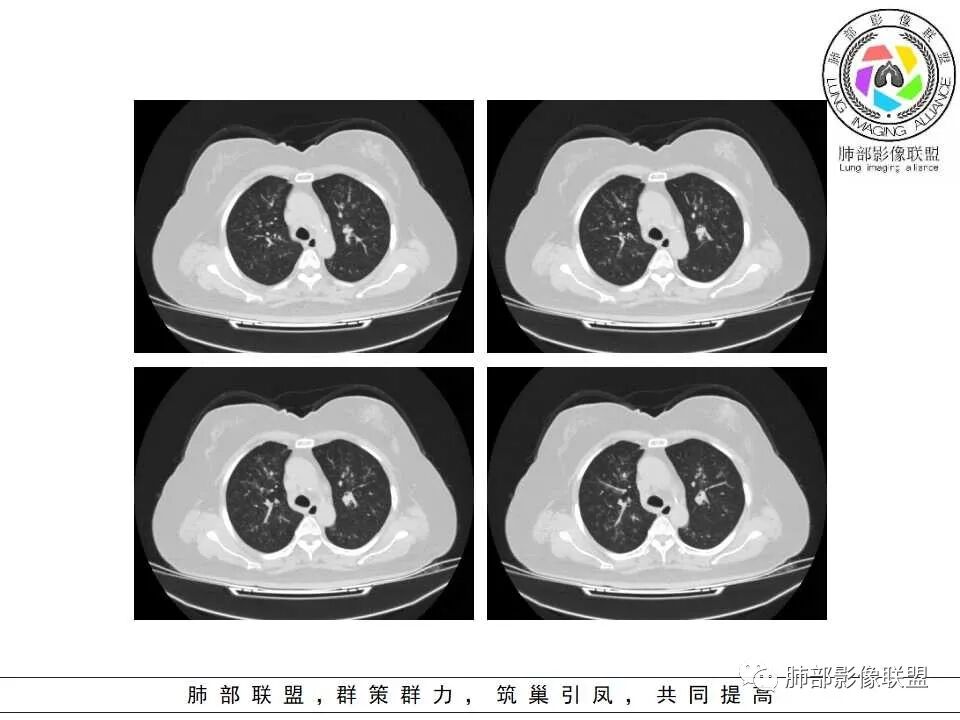

两肺叶支气管壁增厚,边缘模糊,见多发树芽及腺泡结节,边界不清,非对称性分布,CRP和WBC显著增高,抗炎无效,急性过敏性肺泡炎,与曲霉菌鉴别。

老年女性,发现白细胞升高两年,此次入院多次查外周血白细胞>30*10^9/L,淋巴降低,CRP显著升高,但病程中无发热,以细菌性炎不好解释;CT提示有脾大,结合外周血象,首先考虑存在血液系统疾病(白血病)基础,且未系统诊治;肺部CT提示双肺中轴间质增粗,伴随支气管管壁增厚?多发树丫及腺泡结节,部分呈点晕征,可见肺动脉分枝增粗,一元论考虑白血病肺部浸润;二院论考虑白血病并发气道侵袭曲霉。以患者病程进展看,更倾向于白血病肺部浸润。

1.病灶沿支气管分布的特点相当明显,相应支气管壁广泛增厚。这种与支气管关系极为密切的片影和/或结节影,常高度提示气道相关感染,如支气管肺炎。

2.患者两肺多发病变,具有广泛性。如此广泛分布更多见于免疫低下的机会性感染。

3.支气管壁广泛增厚对气道侵袭性曲霉病具有一定的提示意义。注意患者没有支气管扩张,临床也未提供IGE等实验室资料。

一,气道侵袭性曲霉病(PNTA)

1.器官支气管管套样壁增厚和/或支气管扩张,注意壁增厚较均匀,和/或伴有播散性小片影及结节影,注意这些小片影或结节影边界有时较普通炎性病灶清楚。

3.易形成空洞,常无液平面。注意哪些一两周内出现的多发空洞病灶,形成空洞也往往靠边。

二.血管侵袭性肺曲霉病

1.多见于血液恶性肿瘤及造血干细胞移植患者。两肺多发,多见磨玻璃晕,有时病灶基底贴近胸壁形成楔形影。

2.很少支气管壁增厚,也无支气管扩张,少见树芽征。